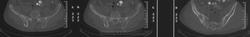

История длинная: образование в ягодичной области заметил 5 лет назад, пунктировали, расценили как ягодичный абсцесс, вскрывали... Сейчас вот КТ сделали, ну и снимки легких, согласно стандарту исследования

угу, биопсия из кости. В литературе читала упоминание о цистоцеркозе костей, но ни в реале, ни на картинках не видела. Кстати, на КТ видны множественные очаги деструкции